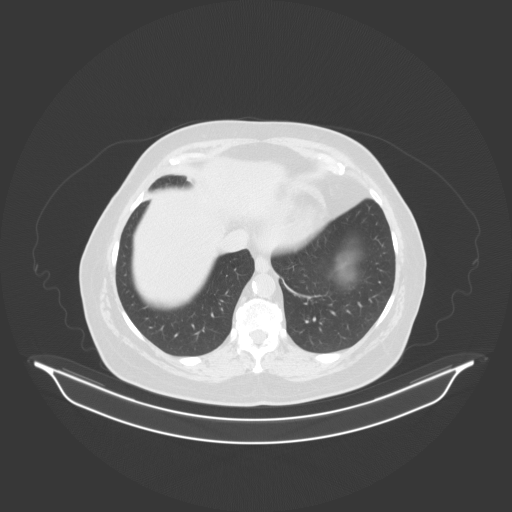

Slice 70 Targeting Evaluation

Slice: Slice_70

Conversion: NATIVE β†’ VENOUS

Targeted Slice 70 - Lung Window Analysis (Generated vs Real Venous)

0.797

Lung SSIM

87.2

Lung RMSE

35.8

Lung MAE

Average Lung Window Metrics Across All Slices (85 slices) - Generated vs Real Venous

0.817

Lung SSIM (Avg)

75.5

Lung RMSE (Avg)

30.5

Lung MAE (Avg)

Original NATIVE CT scan (input)

No window - Raw intensity values